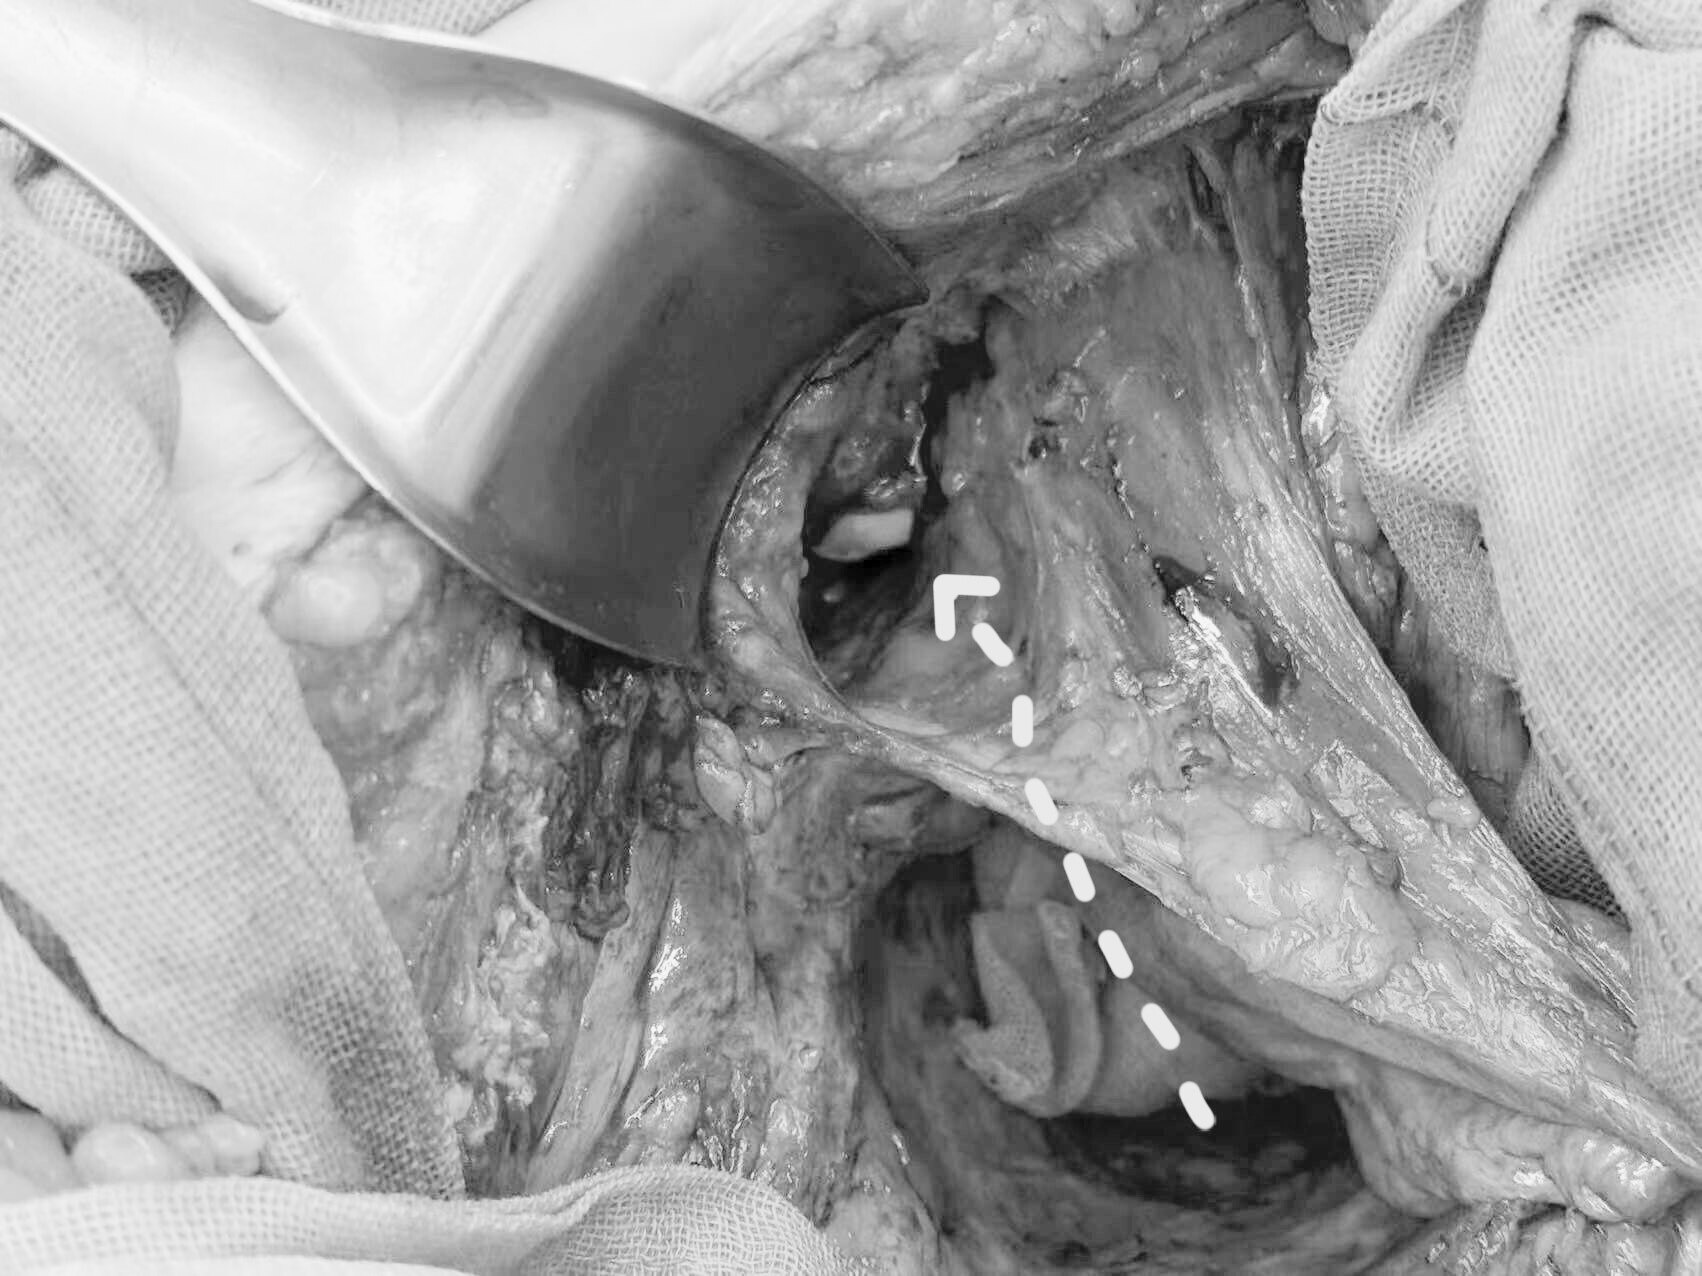

术中发现瘘口蔓延至两侧的闭孔内肌外间隙相通。

经瘘口清除闭孔内肌外间隙的腐烂组织,用石炭酸纱球清除间隙中可能存在的爬行过来的粘膜组织。

经腹打开膀胱腹下筋膜外侧间隙,将闭孔内肌戳洞,经耻骨上放置引流管经闭孔内肌(戳洞)至闭孔内肌外间隙。

【箭头所指:经肛管瘘口伸进的手指,经闭孔内肌外间隙,再经闭孔内肌(打洞)到膀胱腹下筋膜外间隙。】